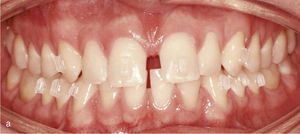

Corrección de la angulaciónCon el sistema Invisalign se puede corregir la angulación de dientes anteriores inclinados. Con dicho fin en los dientes movidos deberían utilizarse ataches que ofrecen un mayor anclaje. El caso de la figura 2 presenta los dientes 11 y 21 en mesioversión con un diastema y un gran triángulo negro interdental. Por medio de los ataches se corrigió la angulación de las coronas 11 y 21 y se cerraron el diastema y el triángulo negro con el sistema Invisalign (fig. 2b).

Sector anterosuperior con dientes 11 y 21 en mesioversión y triángulo negro interdental (a). Se colocaron ataches rectangulares verticales en los dientes 11 y 21 y en los anteriores adyacentes. Resultado del tratamiento después de enderezar los dientes 11 y 21 y de cerrar el triángulo negro (b).